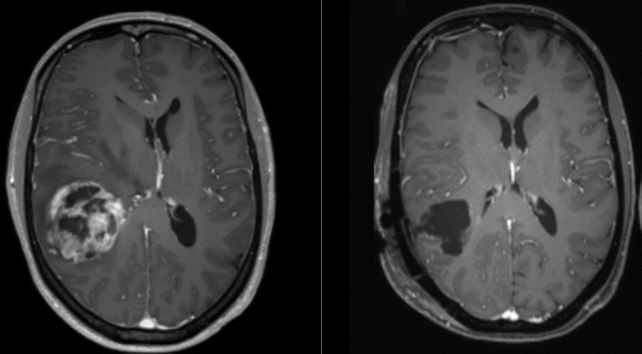

Glioblastoma tumors are highly aggressive, hard to detect early, and deactivate our body's typical immune response, making them challenging to target with traditional cancer therapies.

They're also very hard to reach, given they form in the brain or elsewhere along our delicate central nervous systems.

This nasty cancer impairs brain functions by causing swelling in surrounding healthy tissues, compressing them, and stealing their blood supply.